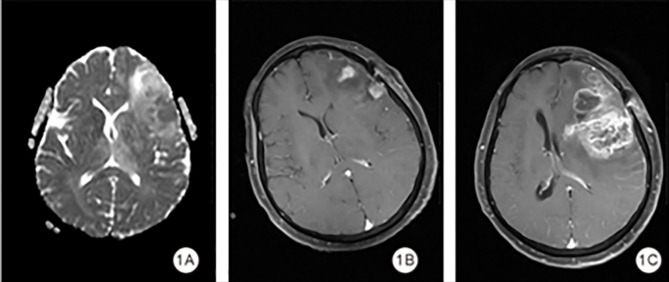

背景:本研究旨在评价表观扩散系数(ADC)值、水肿程度和全身免疫炎症指数(SII)对高级别胶质瘤(HGG)术后早期复发的预测价值。方法:本回顾性研究分析2018年5月至2023年6月在湖南省第二人民医院接受手术治疗的HGG患者的数据。患者分为早期复发组(术后6个月内)和非早期复发组。采用受试者工作特征(ROC)曲线建立基于ADC、水肿程度和SII的HGG早期复发预测模型。结果:共纳入68例HGG患者,其中早期复发20例(29.5%)。早期复发组与非早期复发组患者年龄、肿瘤大小、水肿程度、病理分级差异均有统计学意义(P < 0.05)。肿瘤ADC的ROC曲线下面积(AUC)为0.623 (95% CI: 0.461 ~ 0.786),敏感性为0.500,特异性为0.854;水肿程度为0.652 (95% CI: 0.517-0.787),敏感性为0.900,特异性为0.458;SII为0.781 (95% CI: 0.663-0.900),敏感性为0.750,特异性为0.729。联合模型的AUC为0.823 (95% CI: 0.715-0.931),敏感性为0.800,特异性为0.708。结论:综合评价肿瘤ADC值、SII、水肿程度对HGG早期复发具有预测价值。

Background: This study aimed to evaluate the predictive value of apparent diffusion coefficient (ADC) values, degree of edema and the systemic immune-inflammation index (SII) for early postoperative recurrence in high-grade gliomas (HGG).

Methods: This retrospective study analyzed data from patients with HGG who underwent surgery at the Second People's Hospital of Hunan Province between May 2018 and June 2023. Patients were divided into early recurrence (within six months post-surgery) and non-early recurrence groups. Receiver operating characteristic (ROC) curves were used to develop predictive models for early recurrence of HGG based on ADC, degree of edema and SII.

Results: A total of 68 patients with HGG were included, of whom 20 (29.5%) had early recurrence. Significant differences were observed between the early recurrence and non-early recurrence groups in age, tumor size, degree of edema, and Pathologic grading (all P < 0.05). The area under the ROC curve (AUC) for tumor ADC was 0.623 (95% CI: 0.461-0.786) with a sensitivity of 0.500 and a specificity of 0.854; for degree of edema, it was 0.652 (95% CI: 0.517-0.787) with a sensitivity of 0.900 and a specificity of 0.458; and for SII, it was 0.781 (95% CI: 0.663-0.900) with a sensitivity of 0.750 and a specificity of 0.729. The combined model yielded an AUC of 0.823 (95% CI: 0.715-0.931) with a sensitivity of 0.800 and a specificity of 0.708.

Conclusion: The combined evaluation of tumor ADC values, SII, and the degree of edema offers predictive value for early recurrence in HGG.